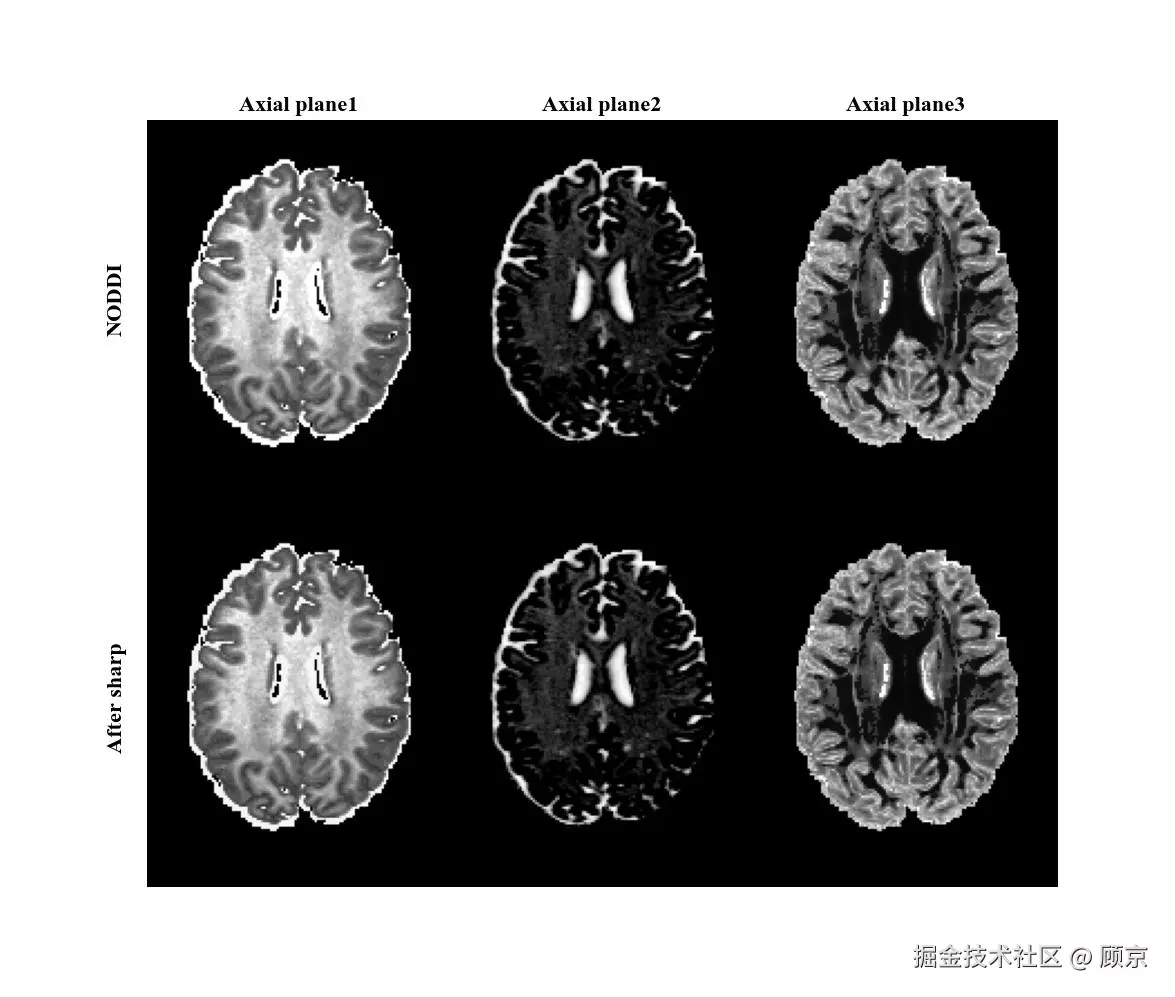

锐化

图像锐化可以补偿图像的轮廓,增强图像的边缘及灰度跳变的部分,使图像变得清晰。这不是降级操作,是增强操作,不过也一起整理在这儿吧,如图4所示。

sharp.jpeg

图4 锐化操作